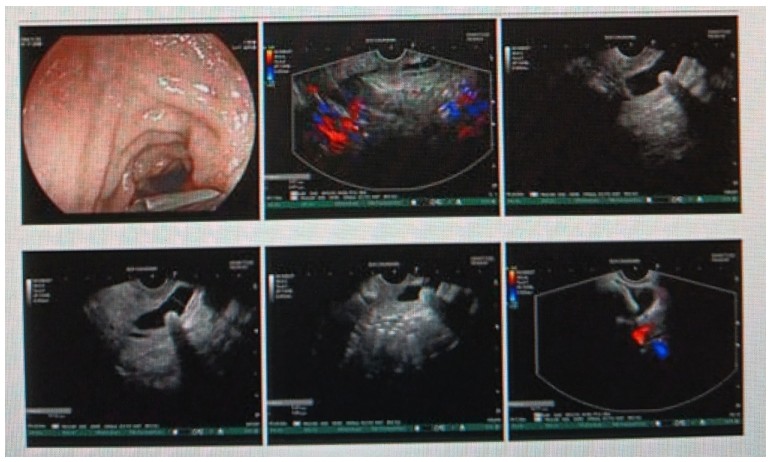

消化內(nèi)科肝病亞??茍F(tuán)隊(duì)詳細(xì)討論,分析患者情況后,取消了周女士的肝穿刺活檢檢查,建議患者先行超聲胃鏡下膽胰掃查。在內(nèi)鏡醫(yī)師第三只眼——超聲胃鏡的掃查下,發(fā)現(xiàn)引起周女士肝功能受損的罪魁禍?zhǔn)?/span>原來是膽總管末端結(jié)石!伍友興主任醫(yī)師帶領(lǐng)團(tuán)隊(duì)給予患者行ERCP下取石后,周女士未再出現(xiàn)腹痛,肝功能恢復(fù)正常。

無獨(dú)有偶,劉先生也為反復(fù)出現(xiàn)肝功能受損到多家醫(yī)院就診檢查,未能找到原因,來到衡陽(yáng)市中心醫(yī)院消化內(nèi)科就診,希望能在肝穿刺活檢下得出病因。在行肝穿刺活檢之前,醫(yī)生建議劉先生行超聲胃鏡膽胰掃查,發(fā)現(xiàn)引起劉先生反復(fù)肝功能受損原因,亦是膽總管結(jié)石引起,在ERCP術(shù)取石術(shù)后,患者肝功能恢復(fù)正常,未再出現(xiàn)異常情況。

張丹霞主任醫(yī)師介紹,超聲內(nèi)鏡通過胃十二指腸自然腔道,可以將探頭貼近相應(yīng)的位置,近距離的觀察胰腺及膽道系統(tǒng),準(zhǔn)確捕捉到直徑小于5毫米的胰腺異常病灶及膽道系統(tǒng)病灶。而體表B超常受皮膚、脂肪或腸道氣體干擾。CT或磁共振檢查只能提供靜態(tài)圖像,且對(duì)膽胰管陰性結(jié)石或是未引起明顯膽管梗阻性的結(jié)石檢查有局限性,因此對(duì)于有輕微腹痛合并肝功能受損的患者,建議常規(guī)行超聲胃鏡下膽胰掃查。超聲胃鏡、腹部彩超、腹部CT、腹部MRI同為診斷膽管細(xì)微病變的四架馬車,在膽總管結(jié)石診斷方面,超聲胃鏡膽胰掃查同ERCP一樣,是敏感性高、特異性強(qiáng)的診斷方法。超聲胃鏡發(fā)現(xiàn)可疑病變,可以完成穿刺活檢,還可行囊腫穿刺引流、膽管減壓、消融術(shù)等。